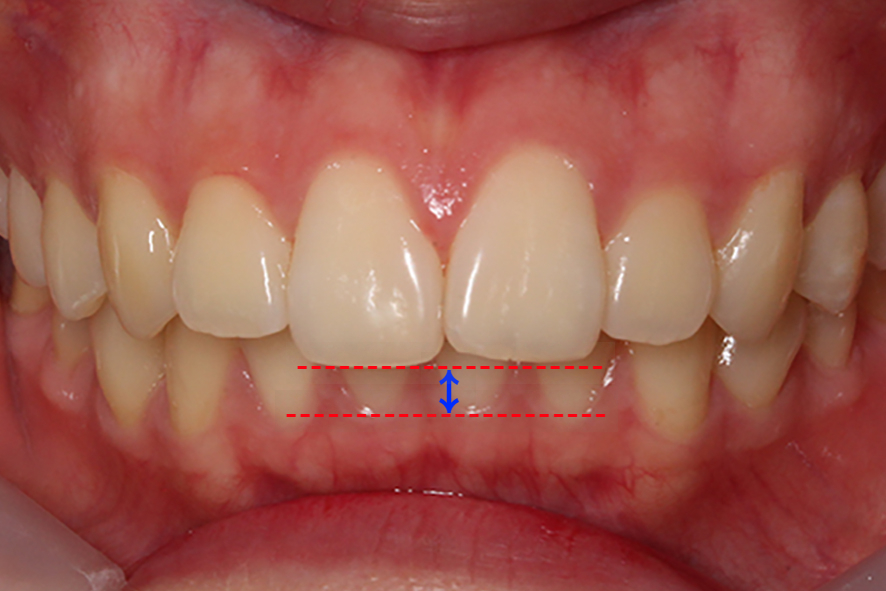

입돌출 교정 전 치아의 구내 사진을 보면

상하악을 교합했을 때 전치부의 모습이

하악이 거의 보이지 않는 deep bite

성향을 보이는 모습인데요,

상대적으로 하악의 발달이

미약하다보니 과도하게 발달한

상악으로 인해 위와 같은 증상을

보일 수 있습니다.

overbite 사진을 보면 윗니가

아랫니에 닿지 않는 모습으로

돌출감이 느껴지는 모습인데요,

정면 사진과 마찬가지로 치아의

돌출감은 심하지 않은 것으로 보입니다.